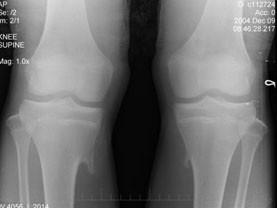

问题 14岁男性患者,发现双膝关节包块1天,双膝关节摄片如图所示,最佳的诊断是 ( )

选项 A、软骨肉瘤 B、骨肉瘤 C、骨软骨瘤 D、局限性骨皮质增厚 E、骨瘤

答案 C